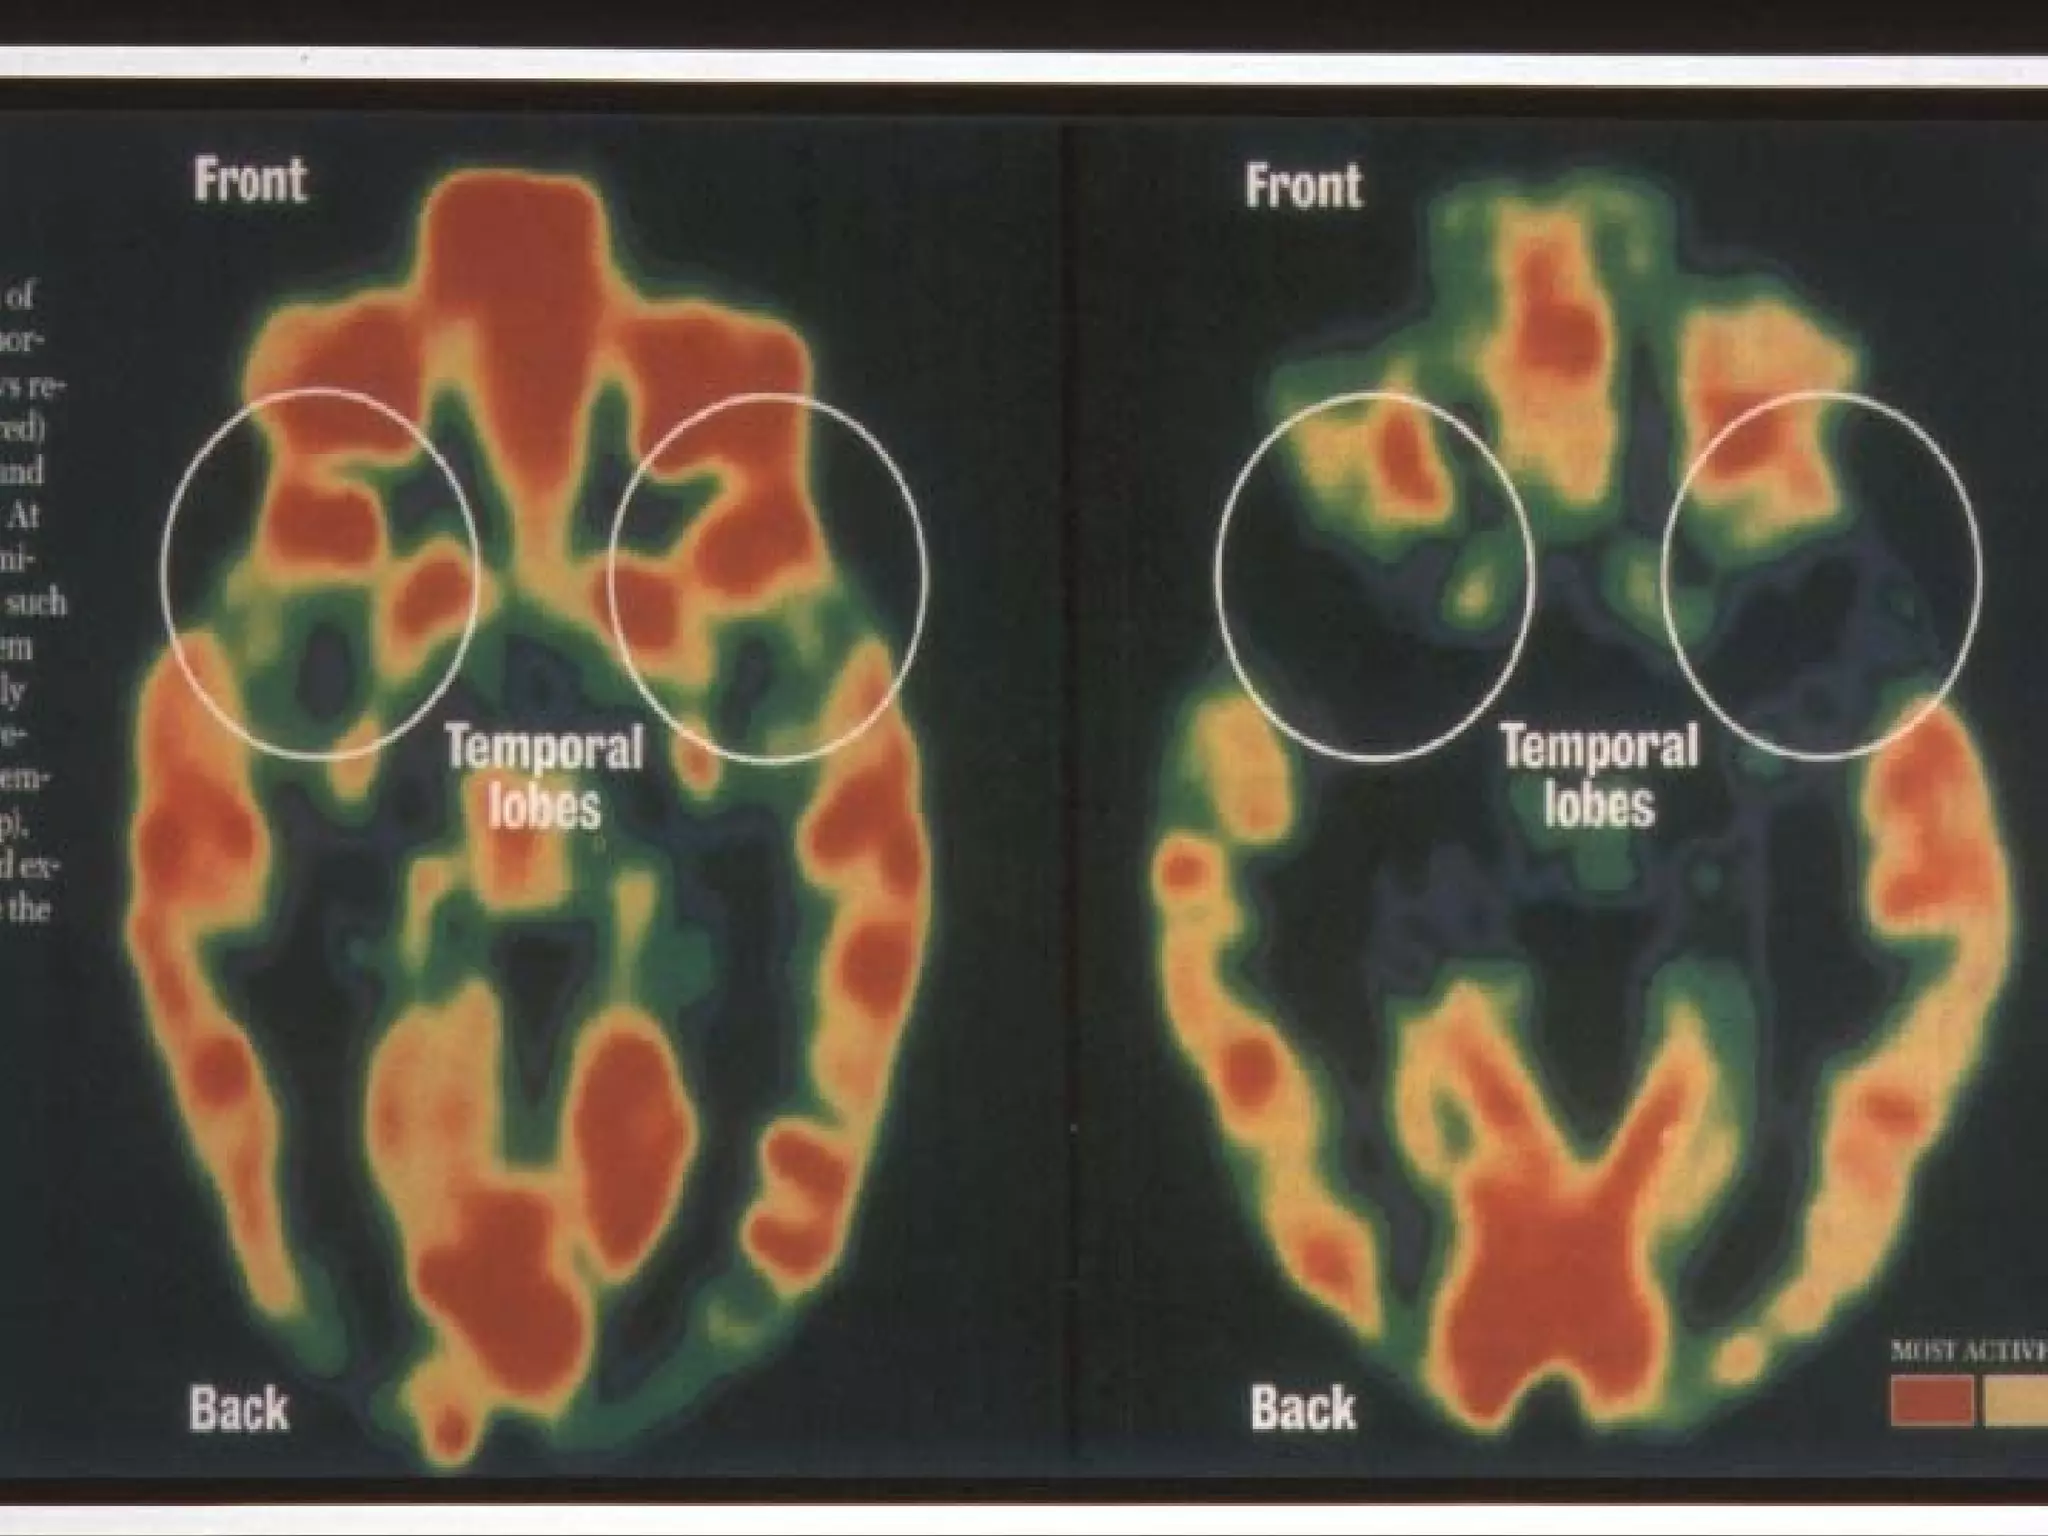

   Babies of depressed mothers:

- nearly half show reduced brain activity

- much lower levels of left frontal brain activity

(joy; interest; anger)